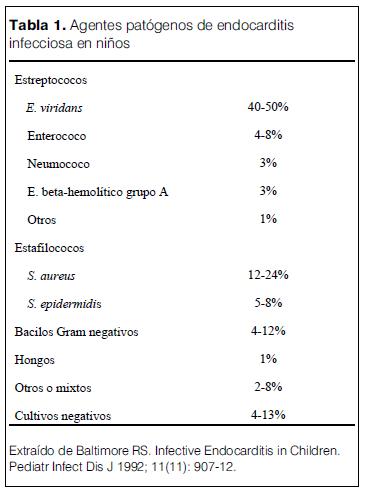

Los agentes causantes de EI en los pacientes pediátricos se revisan en la tabla 1.